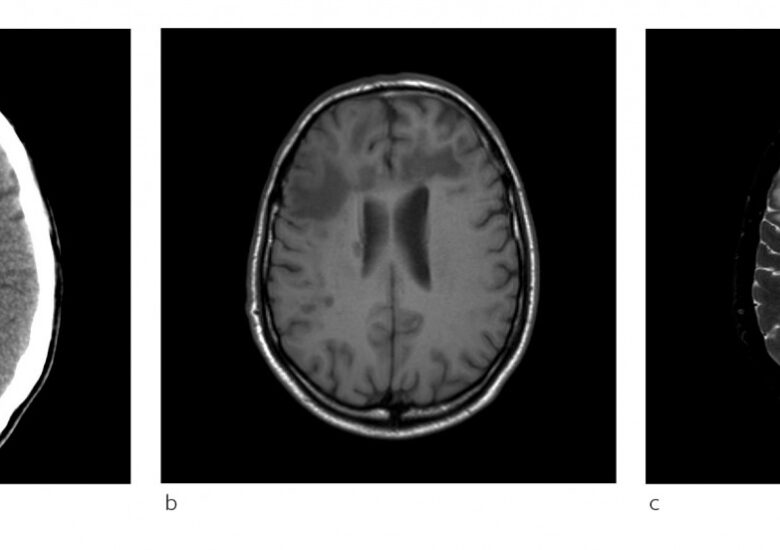

O prezentare generală a leucoencefalopatiei multifocale progresive (LMP). O infecție gravă a creierului

Leucoencefalopatia multifocală progresivă (LMP) este o boală gravă în care virusul John Cunningham (JC) infectează mai multe zone ale creierului, dăunându-l pe măsură ce infecția se agravează rapid și provocând